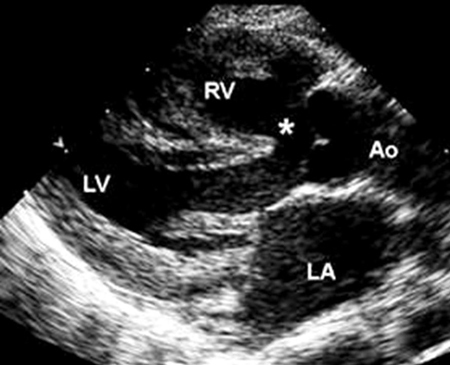

TOF is the most common cyanotic CHD, representing 4% to 8% of all defects, and can occur as a solitary cardiac lesion, or as part of a genetic syndrome, the most common of which is DiGeorge syndrome (a microdeletion of 22q11.2).[40] It consists of 4 abnormalities: outlet ventricular septal defect (VSD), right ventricular outflow tract (RVOT) obstruction, an aorta that over-rides the crest of the ventricular septum, and RV hypertrophy, a result of RVOT obstruction.[Figure caption and citation for the preceding image starts]: Parasternal long axis echocardiographic image in a patient with tetralogy of Fallot. The aorta (Ao) overrides the VSD (*). (LA) left atrium; (RV) right ventricle; (LV) left ventricleImage courtesy of Patrick W. O'Leary, MD [Citation ends].